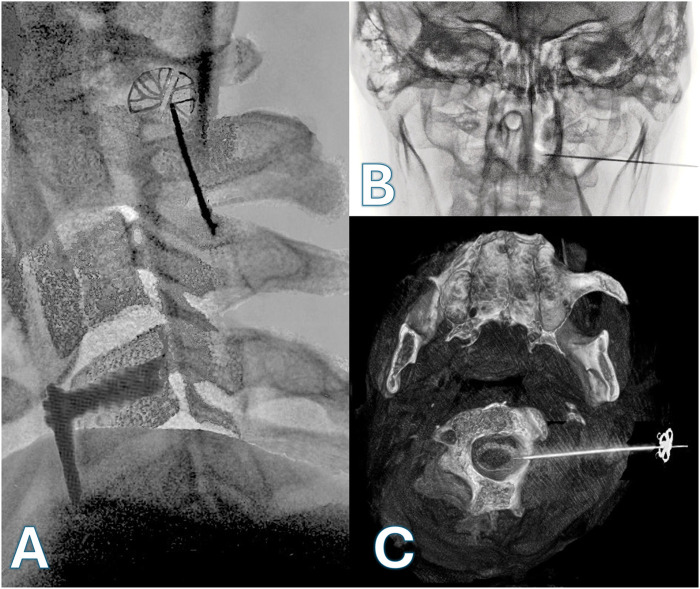

Spasticity is a neurological disorder that disrupts the regulation of muscle tone following an injury to the central nervous system, such as spinal cord injury. Baclofen is the most effective medication for treating spasticity and can be delivered via a pump connected to an intrathecal catheter. The catheter is typically inserted via a lumbar punction and advanced up to the level corresponding to the disturbing spasticity. But this may not be possible, especially when cervical level is involved. We present the case of a patient with severe spasticity after a traumatic cervical spinal cord injury who successfully underwent a lateral C1-2 puncture for placement of a retrograde catheter to the C4 level, after an unsuccessful attempt at catheter placement via a lumbar puncture. The patient experienced a significant reduction in spasticity with no reported worsening during the 8 months follow-up period. The catheter placement via a lateral C1-2 puncture guided by innovative imagery with 3D reconstruction, may serve as an effective and safe alternative to deliver baclofen at the cervical level. Relevance of cervical ITB is discussed and issues involved are considered. The mechanism of action of ITB at cervical level, which is far from fully clarified, is crucial to reach the best clinical outcome and avoid si de effects and complications. Few clinical cases were published; hence the importance to present this case.